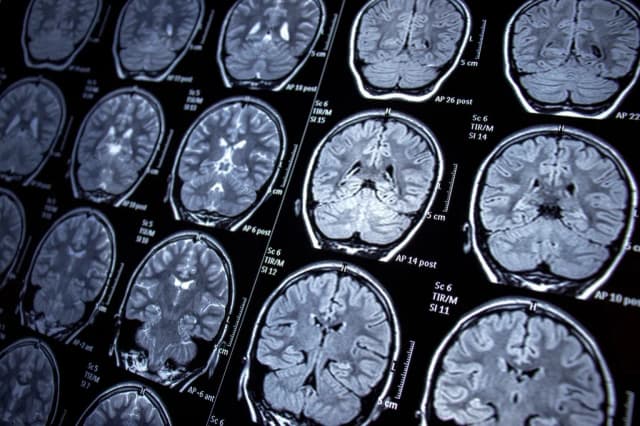

Padaczka - jakie badania są kluczowe w diagnostyce tego schorzenia?

Poznaj kluczowe badania diagnostyczne padaczki, takie jak EEG i MRI. Dowiedz się, jakie testy są istotne w diagnostyce epilepsji i jakie badania przy padaczce.